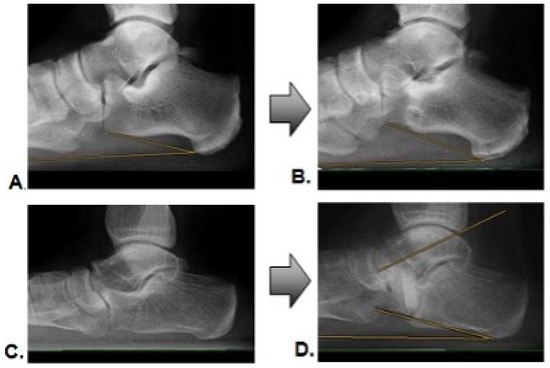

As part of the six-month postoperative clinical follow-up, native weight-bearing radiological imaging was conducted. The radiologically determined incorporation of the bone graft was evaluated according to the criteria of Worth et al. (see Figure 2) by two independent, blinded investigators [20]. Grades III and IV were considered successful incorporation.

Radiographic foot alignment evaluation was performed by measuring the talo-navicular coverage angle (TNCA), the talo-first metatarsal angle (TFMA) and the calcaneal pitch angle (PCA) in the dorsoplantar and lateral radiographic imaging, preoperatively and in the postoperative course.

3.3. Incorporation Rate

Within six months of the postoperative follow-up, the AG showed a successful incorporation of the transplanted autologous bone grafts in 26 transplants (96.3%). Only one transplant failed to demonstrate sufficient consolidation (3.7%). For the XG at a six-month follow-up, nine transplants (57%) were incorporated. Seven bone grafts (43%) showed grade I or II, according to Worth et al. [20]. Figure 3 gives an example of a successful incorporation (Figure 3A,B) and an example of a failed incorporation with a loss of correction (Figure 3C,D).

Figure 3. Radiographic example of pre- and postoperative images with successful incorporation (A,B), and loss of correction with incomplete incorporation (C,D).